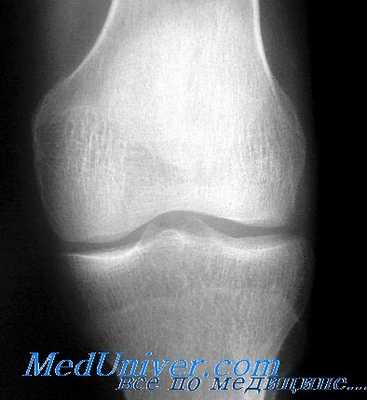

Суставы. Анатомически, как известно, сустав представляет собой прерывное, полостное, подвижное соединение. Рентгенологическое понятие сустава резко отличается от анатомического. Большая часть суставных элементов имеет мягкотканную структуру и прямого отображения на снимке не дает. Рентгенологически обрисовываются только два суставных компонента: суставные концы костей и суставная щель. Суставной конец каждой кости имеет строго определенную форму и структуру, соответствующую функции сустава.

На снимке суставные концы четко контурированы и окаймлены хорошо выраженной ровной «гладкой» компактной костной пластинкой, являющейся непосредственным продолжением тени коркового слоя метафиза. Эту часть кортикального слоя, находящуюся под суставным хрящем, принято называть замыкательной или замыкающей (субхондральной) пластинкой. Замыкающая пластинка суставной впадины в нормальных условиях всегда значительно толще субхондральной пластинки суставной головки.

Суставная щель проявляется на рентгенограмме в виде полосы просветления той или иной высоты и формы, которая проекционно соответствует суставным хрящам, дискам, менискам и внутрисуставным связкам, а также истинной анатомической суставной щели. Однако удельный вес анатомической суставной щели в образовании рентгеновской щели является ничтожным. Для каждого сустава рентгеновская суставная щель имеет определенную высоту и форму. У детей суставная щель широкая, а у стариков узкая, вследствие изношенности хряща. Наиболее широкие рентгеновские щели у коленных и бедренных суставов (4—6 мм).